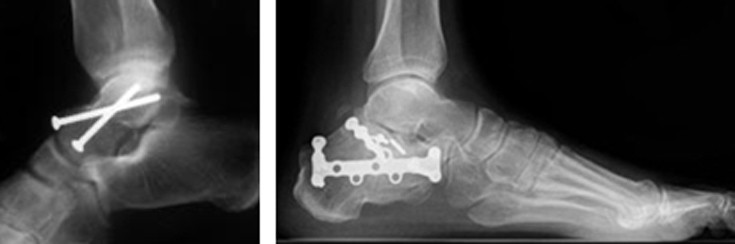

Για την διάγνωση των δύο αυτών καταγμάτων, είναι απαραίτητη η ακτινογραφία και η αξονική τομογραφία.

Και τα δύο κατάγματα χρειάζονται χειρουργική αντιμετώπιση (οστεοσύνθεση).